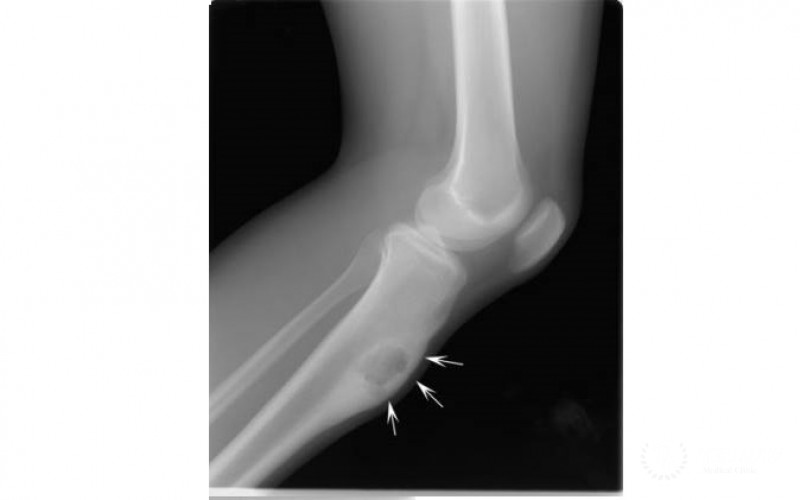

Специалист после осмотра больного проведет детальное исследование места заболевания с применением рентгенографии, УЗИ, МРТ.